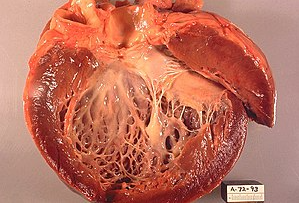

알코올성 심근병증(Alcoholic Cardiomyopathy, ACM)은 과도한 음주가 심장 근육에 독성을 미쳐 발생하는 심장 질환입니다. 이 질환은 주로 심장의 확장성 심근병증(Dilated Cardiomyopathy, DCM) 형태로 나타나며, 심장의 수축 기능이 저하되고 심장 크기가 커지는 특징이 있습니다. 알코올이 지속적으로 섭취되면 심장의 근육 세포가 손상되며, 결과적으로 심장의 펌프 기능이 약해져 혈액 순환이 원활하지 않게 됩니다.

이 질환은 심장 근육의 수축력이 감소하고, 심장의 벽이 얇아지고, 심장 크기가 확장되는 상태를 일으킵니다. 이로 인해 심장이 혈액을 효율적으로 순환시키지 못하고, 심부전을 초래할 수 있습니다. 심부전은 심장이 몸에 필요한 충분한 혈액을 공급하지 못하게 되면서 여러 가지 증상들이 발생하는 상태입니다.

알코올성 심근병증에서 가장 흔하게 발생하는 형태는 확장성 심근병증입니다. 이는 심장 근육이 약해지고 확장되어 심장의 기능이 저하되는 상태입니다.

- 심장의 확장: 심장 근육이 손상되면서 심실이 비대해지고 확장됩니다. 이로 인해 심장의 펌프 기능이 저하되고, 혈액을 충분히 순환시키지 못하게 됩니다.

- 심근의 얇아짐: 심근이 약해져 근육 세포가 손상되면 심장의 벽이 얇아지고, 심장 수축력이 떨어집니다.